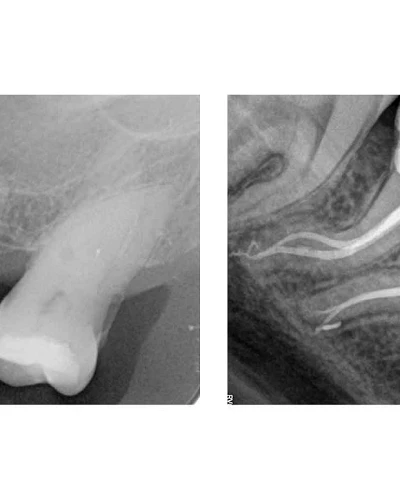

Casos Complejos de Endodoncia

Nos especializamos en el manejo de casos endodónticos de alta complejidad que requieren una pericia clínica avanzada. Este servicio se centra en el tratamiento de conductos severamente calcificados, curvaturas radiculares complejas y anatomías internas inusuales. Utilizando microscopía dental de alta magnificación e instrumental ultrasónico especializado, logramos navegar vías obstruidas para asegurar una desinfección y sellado completos, preservando piezas dentales que de otro modo podrían ser extraídas.